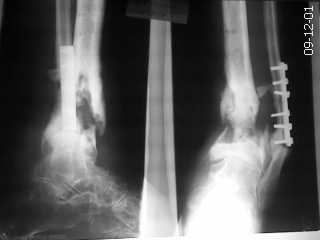

Поступил пациент с хроническим остеомиелитом. варусной установкой дистального отломка.

Пациент 35 лет. Оперирован по поводу перелома в ЦРБ. В дальнейшем нагноение-удаление

пластины большеберцовой кости. В настоящее время имеется варусная установка голени,

укорочение конечности. Имеется рана с гнойным отделяемым. Ходит с помощью костылей.